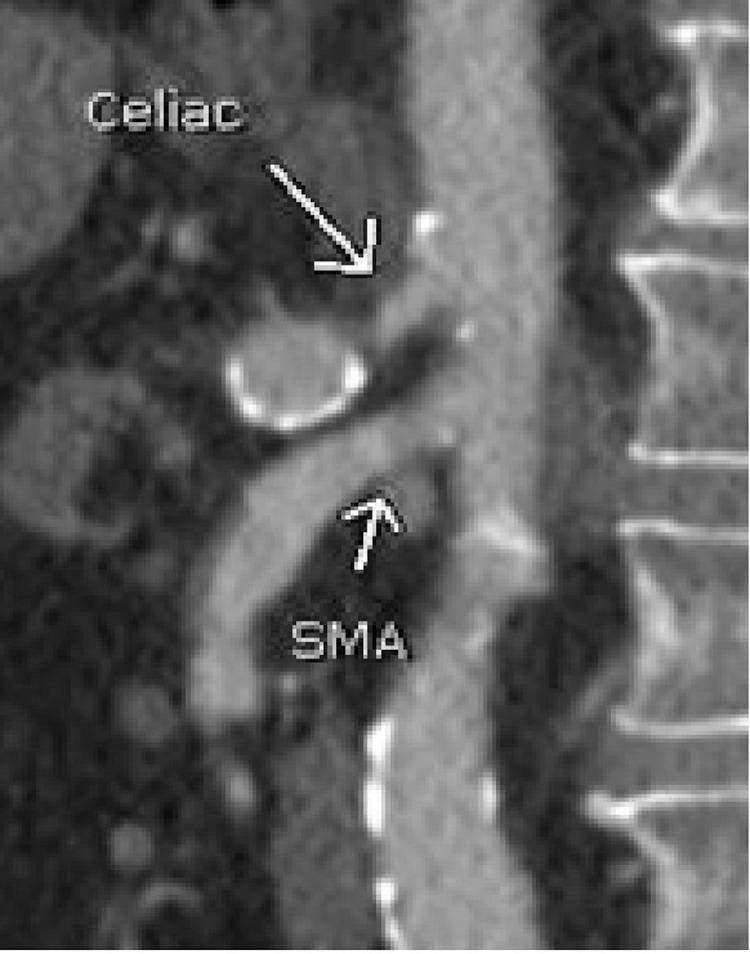

The etiology of large artery aneurysms has long been established as secondary to atherosclerotic disease and degenerative changes in the vessel walls. Less common, are aneurysms of the visceral arteries; the splanchnic and renal arteries. Rarer yet, are inferior mesenteric artery aneurysms, accounting for approximately 1% of visceral artery aneurysms. While causes range from inflammatory to congenital disease, a proposed etiology of proximal, solitary inferior mesenteric artery aneurysms, is correlated to the "jet disorder phenomenon," first described in a 1990 case report by Sugrue, and Hederman. This paradigm states that aneurysm formation may occur secondary to celiac and superior mesenteric artery occlusion, causing increased, and turbulent arterial flow distally. We present a case that demonstrates a small inferior mesenteric artery aneurysm without findings of celiac or superior mesenteric artery stenosis or occlusion. This patient did, however, have a large thrombosed common hepatic artery aneurysm which may serve as an alternate cause of jet disorder phenomenon. The findings in this case offers support for focused screening of proximal arterial vasculature when an inferior mesenteric artery aneurysm is encountered.

大动脉动脉瘤的病因长期以来一直被认为是继发于动脉粥样硬化疾病和血管壁的退行性变化。内脏动脉的动脉瘤较少见,如内脏和肾动脉。更罕见的是肠系膜下动脉动脉瘤,约占内脏动脉动脉瘤的1%。虽然病因范围从炎症性疾病到先天性疾病,但一种关于近端孤立性肠系膜下动脉动脉瘤的病因假说与“喷射紊乱现象”相关,该现象最早在1990年Sugrue和Hederman的病例报告中描述。该范例指出,动脉瘤形成可能继发于腹腔干和肠系膜上动脉闭塞,导致远端动脉血流增加和紊乱。我们报告一例病例,该病例显示一个小的肠系膜下动脉动脉瘤,未发现腹腔干或肠系膜上动脉狭窄或闭塞。然而,该患者有一个大的血栓形成的肝总动脉瘤,这可能是喷射紊乱现象的另一个原因。该病例的发现为遇到肠系膜下动脉动脉瘤时对近端动脉血管进行重点筛查提供了支持。